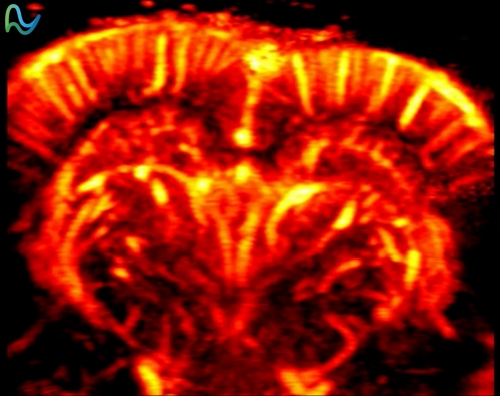

Functional Ultrasound (fUS) Imaging is a high-sensitivity, high-resolution neuroresearch tool that achieves whole-brain functional imaging by detecting microvascular hemodynamic changes. With micron-scale spatial resolution and millisecond-level temporal resolution, it precisely correlates neural activity with blood flow dynamics, providing a novel approach for neuroscience research and brain disease modeling.

Rodent Whisker Stimulation Experiment

The novel fUS (functional ultrasound) brain imaging technology enables real-time tracking of neural activation evoked by whisker stimulation in rats. Square waves represent whisker stimuli, while blue areas depict cerebral blood volume (CBV) responses captured by fUS. The acquired CBV signals correlate with stimulation cycles, demonstrating synchronous activation in somatosensory cortex regions. During stimulation, fUS signals show ~30% amplitude increase, confirming its capability to capture stimulus-evoked brain activity. -

Primate Visual Stimulation Experiment

The novel fUS (functional ultrasound) brain imaging technology enables real-time tracking of cerebral blood volume (CBV) responses in visual cortex regions during diverse visual pattern stimulation.